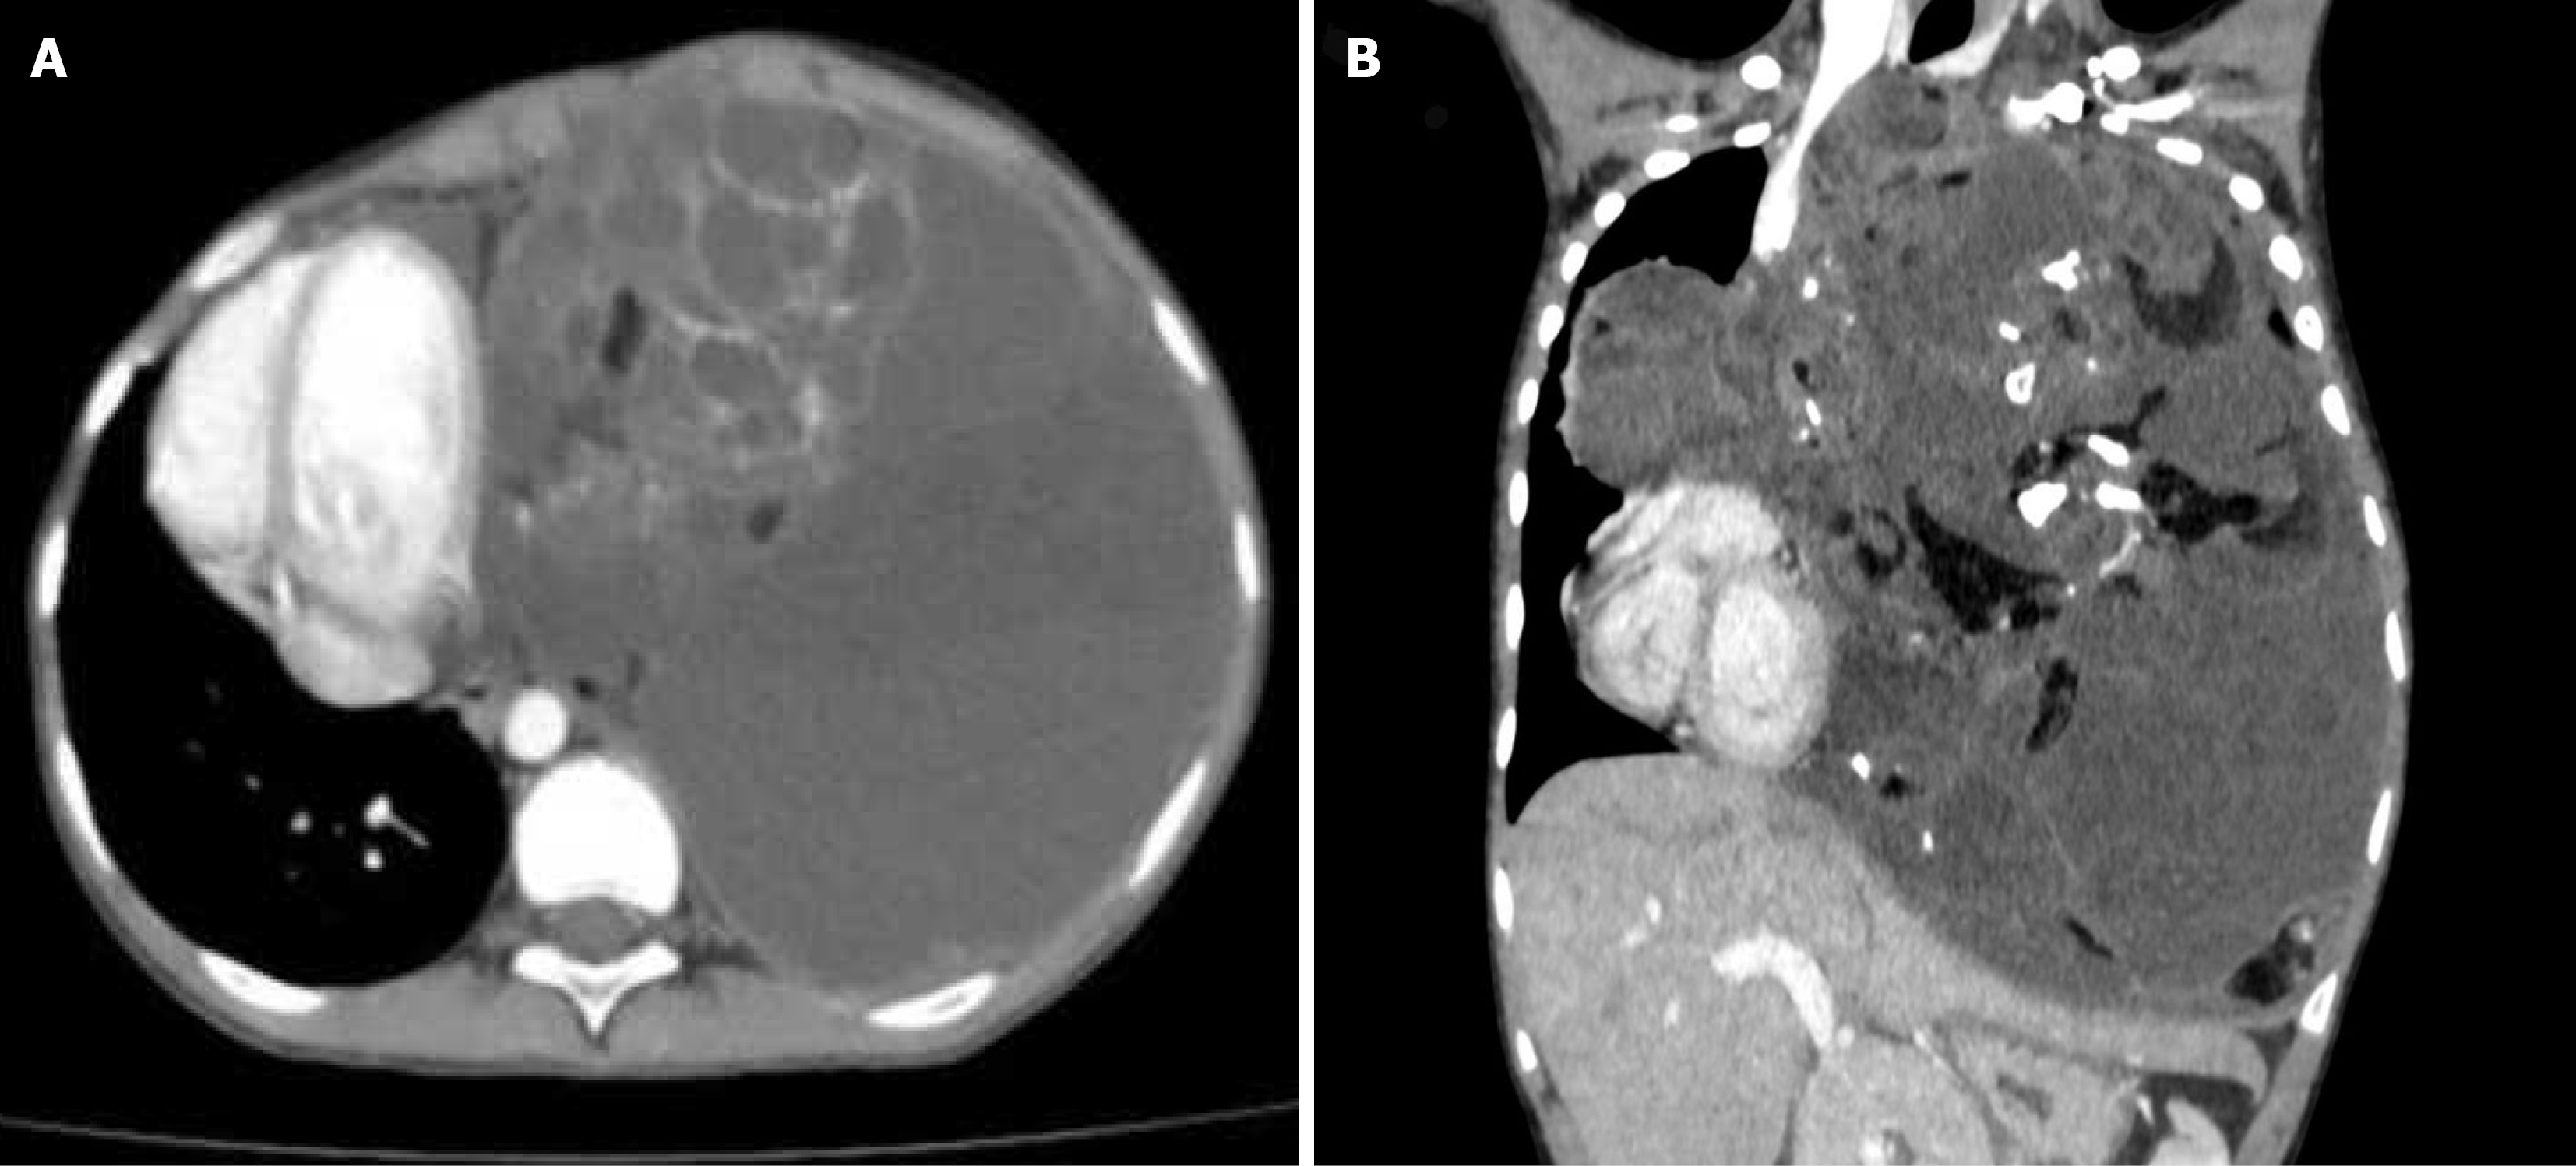

Figure 1 Contrasted chest computed tomography.

A: Axial section; B: Coronal section. Revealed a giant anterior mediastinal mass.